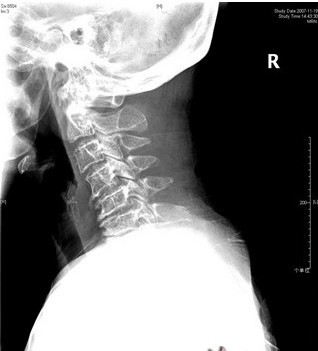

后天退变性因素因为颈椎的退变,导致骨质增生或者椎间盘突出,使椎管的容积量下降以压迫神经,产生一系列症状这种情况也很难通过药物或者自我保健来扩大容积量,只能通过治疗达到缓解症状的作用颈椎管狭窄症主要的治疗方式是手术,通过手术可以扩大椎管容积,清除压迫脊髓或者占用通道的物质,从而达到椎管扩大的目的如果没有产生临床症状,日常生活中多注意保养,以减缓退变,并控制后天。

颈椎管狭窄的治疗需根据病因和病情严重程度选择最佳方案,具体如下一先天性椎管狭窄若为先天性颈椎管骨性狭窄,由于椎管容积先天不足,神经受压风险较高,早期手术干预是最佳选择手术通过扩大椎管容积如椎板切除或成形术,直接解除对脊髓和神经根的压迫,可有效预防神经功能进一步损伤二继发性椎。

颈椎管狭窄通常不能自愈颈椎管狭窄的病因包括颈椎间盘退变椎体后缘骨赘形成黄韧带肥厚等,这些病理改变会导致颈椎管空间逐渐缩小,压迫脊髓和神经根由于颈椎结构存在持续性退变或增生,且神经组织受压后可能发生不可逆损伤,不治疗的情况下症状会逐渐加重,甚至引发四肢瘫痪等严重后果其症状与狭窄。